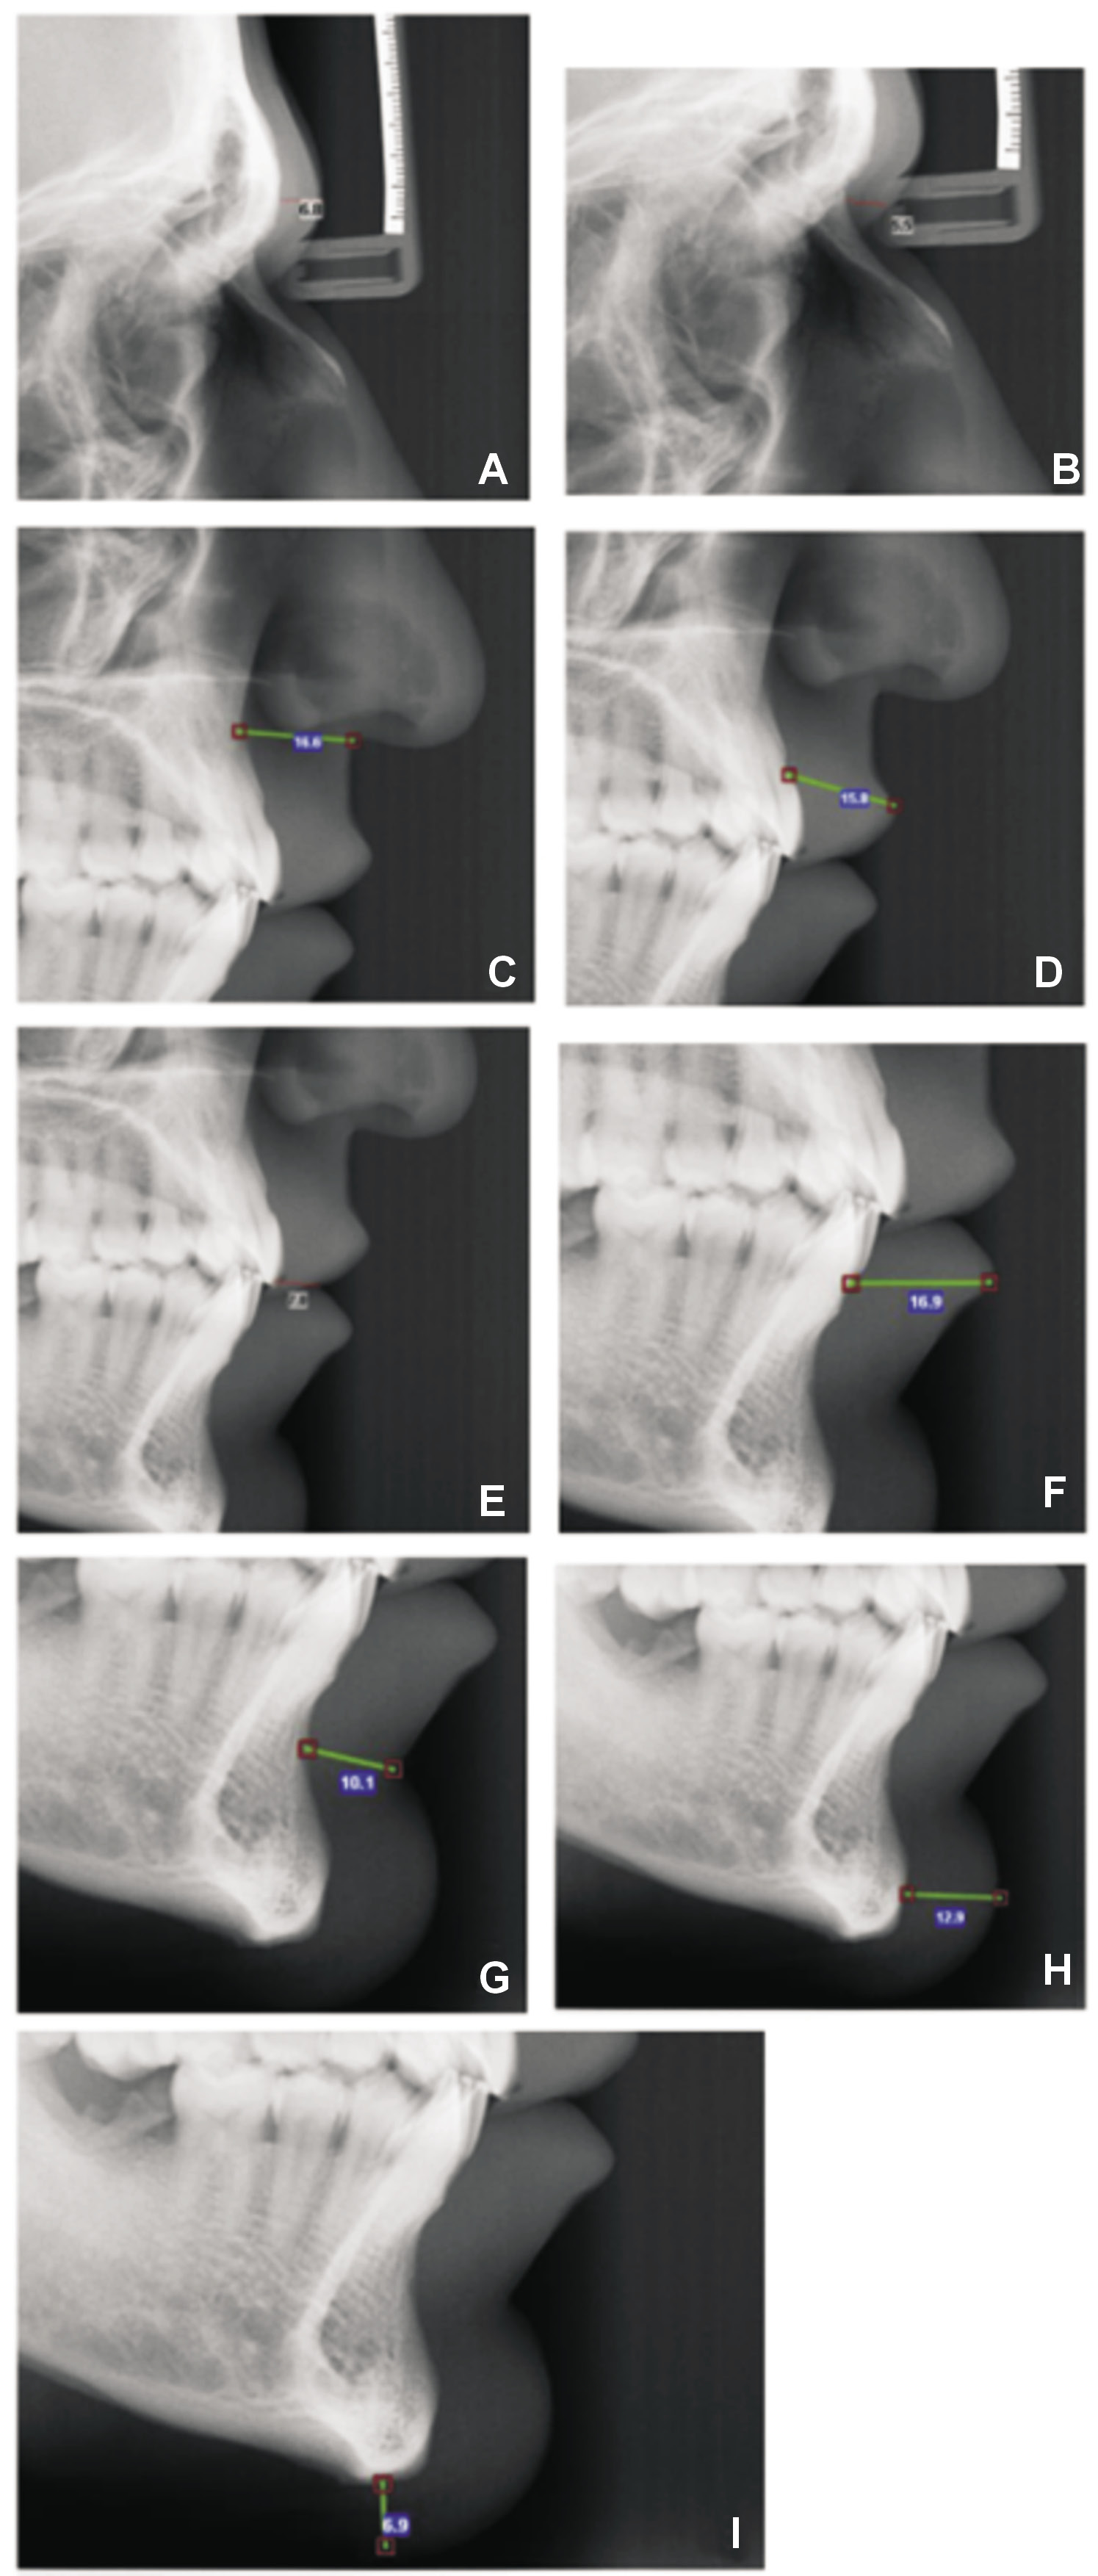

The lateral cephalograms were traced, and 9 hard tissue anatomical landmarks and their corresponding soft tissue analogs were identified according to the literature.1, 4, 5, 6, 7, 8, 9, 10 The landmarks were as follows:

– G–G’-1: glabella region, defined as the linear distance between point G (most prominent point of the frontal bone) and its corresponding soft tissue analog point (Figure 1A);

– N–N’: nasion region, defined as the linear distance between point N and its soft tissue analog point (at the fusion of frontal and nasal bones) (Figure 1B);

– A–Sn: subnasale region, defined as the distance between point A (most concave point of the maxilla) and the subnasale (Sn) (Figure 1C);

– Pr–Ls: distance between the prosthion (Pr) and the upper lip surface (labrale superius (Ls)) (Figure 1D);

– J–St: distance between point J (most labial point of upper incisors) and the contact point of the upper and lower lips (stomion (St)) (Figure 1E);

– Id–Li: distance between the infradentale (Id) (most anterior and superior point on the alveolar ridge between lower central incisors) and the lower lip surface (labrale inferius (Li)) (Figure 1F);

– B–B’: distance between point B (most concave point of the mandibular symphysis) and point B’ (labiomentale or the most concave point of the soft tissue of mandibular symphysis) (Figure 1G);

– Pog–Pog’: distance between the pogonion (Pog) or most prominent point of the chin and its soft tissue analog point (Figure 1H);

– Me–Me’: distance between the most inferior point of the mandible (menton (Me)) and its soft tissue analog point (Figure 1I).